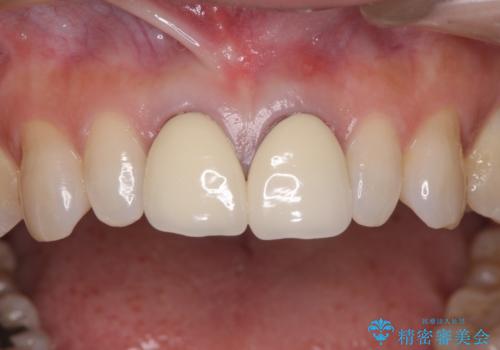

セラミック治療と根管治療を行いました。

金属を使用したメタルボンドクラウンが入っていたため、いつかオールセラミックにしたいときに根管治療も行ったほうが良いとご提案し、今回行いました。

色について

歯と歯肉の境目の色は、歯自体が黒くなっている場合、完全にカバーすることは難しいです。